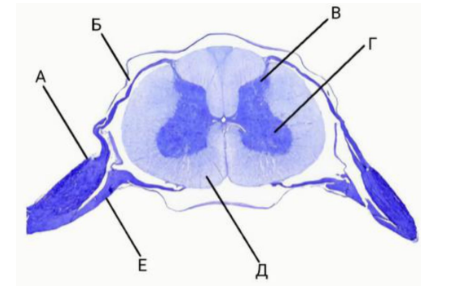

26. Выберите верные утверждения о зонах, обозначенных буквами:

А и Е проводят эфферентный сигнал B

А содержит тела нейронов, отростки которых проходят в Б

В — задние рога

Д- серое вещество

Г содержит тела чувствительных нейронов

Ответ: А содержит тела нейронов, отростки которых проходят в Б, В — задние рога